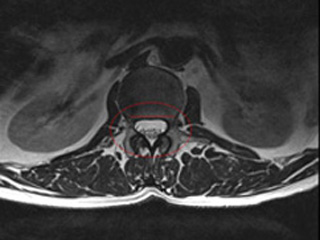

Der chirurgische Eingriff wird mit einem Zugang von Rücken aus durchgeführt und es werden alle Strukturen (Knochen, gelbe Band (Ligamentum flavum), Bandscheiben etc.) entfernt, die auf das Rückenmark, Nervenwurzeln und -bahnen drücken.

- Dekompression des Spinalkanals: Entfernung der Kompression der Nervenwurzel durch Vergrößerung der Nervenwurzelaustrittsöffnungen.

- Laminektomie: Entfernung des hinteren Anteils der Wirbelsäule und damit Vergrößerung des verfügbaren Platz für das Rückenmark. Dieses Verfahren wird bei schweren Stenosen angewendet.